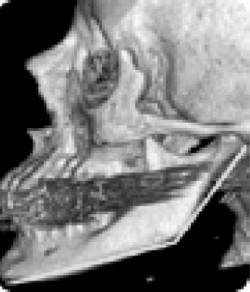

Еще одно сообщение Phys-Org: руководитель службы пластической и реконструктивной хирургии в американской университетской клинике Говард Лэнгстайн (Howard Langstein) на основании своих многочисленных исследований утверждает, что с возрастом происходит изменение угла нижней челюсти (показанные желтым цветом), длина и высота самого тела челюсти (рис. 10).

Иллюстрация к книге — Биогимнастика для лица: система фейсмионика [i_014.jpg]

Рис. 10а. Череп старого человека

А поскольку нижняя челюсть является основной костью лицевой части лица, любые ее изменения влияют на общий вид лица.

Внешне это проявляется в том, что его нижняя часть приобретает более вялые очертания, мягкие ткани провисают, овал теряет свою четкость, снижается тонус кожи щек, подбородка и шеи, в результате чего очертания лица приобретают характерный возрастной вид. Далее Г. Лэнгстайн добавил: «Хотя врачи всегда знали, что кости со временем меняются, но как это проявляется с возрастом – не смогли оценить до конца».